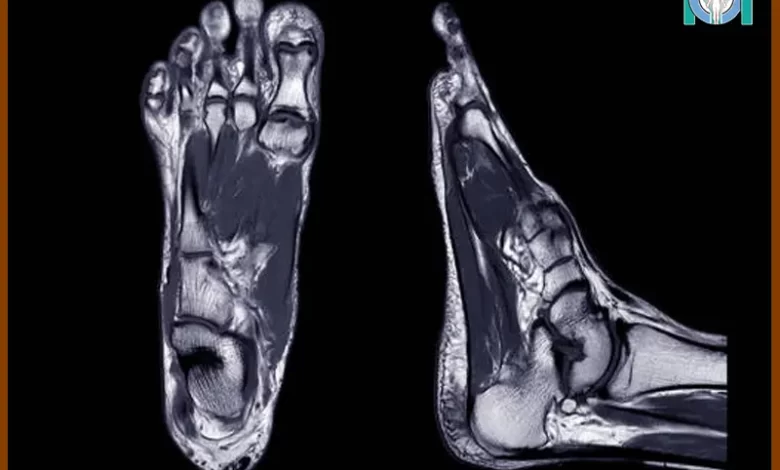

ام آر آی پا یکی از اسکنهای تصویربرداری پزشکی است که برای بررسی استخوانها، ماهیچهها و سایر بافتهای نرم پا استفاده میشود. این اسکن میتواند تصاویر دقیقی از استخوانها و مفاصل پا ارائه دهد و در تشخیص مشکلات مچ پا مانند پیچ خوردگیها و شکستگیها مفید باشد. اگر با علائمی مانند درد، تورم، قرمزی، بیحسی یا کاهش حس پا مواجه شدهاید، پزشکان ممکن است به شما انجام ام آر آی پا را توصیه کنند. در ادامه به بررسی موضوع آمادگی برای انجام ام آر آی میپردازیم.

ام آر آی پا یکی دیگر از اسکنهای تصویربرداری پزشکی است که به بررسی مچ پا، پاشنه پا، تاندون پا، انگشتهای پا و سایر قسمتهای پا میپردازد. این اسکن میتواند تصاویر دقیقی از استخوانها و مفاصل پا ارائه دهد و در تشخیص مشکلات مچ پا مانند پیچ خوردگیها و شکستگیها مفید باشد.

از آنجایی که برخی از ناهنجاریهای تاندونها، رباطها، عضلات، غضروفها و استخوانهای پا در عکسبرداری با اشعه ایکس یا سیتی اسکن قابل مشاهده نیستند، ام آر آی پا میتواند به پزشک کمک کند تا انواع شرایط پزشکی مانند آسیبهای تاندون، رباط، شکستگیهای استخوانی، عفونتها و تومورهای استخوان و مفاصل را تشخیص دهد.

در ام آر آی از میدان مغناطیسی و امواج رادیویی برای تولید تصاویر دقیق از استخوانها، مفاصل، تاندونها، رباطها، ماهیچهها و رگهای خونی استفاده میشود.

به طور خلاصه، ام آر آی مچ پا یک روش تصویربرداری پزشکی است که با استفاده از میدان مغناطیسی و امواج رادیویی، تصاویر دقیقی از استخوانها، مفاصل، تاندونها، رباطها، ماهیچهها و رگهای خونی میگیرد. این روش عدم تشعشعات مضر، دقت بالا در تشخیص ناهنجاریها و قابلیت تصویربرداری غیرتهاجمی دارد. پس از تصویربرداری، نتایج بهصورت گزارشی تفسیر میشوند تا به پزشک معالج کمک کنند تا بهترین روش درمانی را تعیین کند.